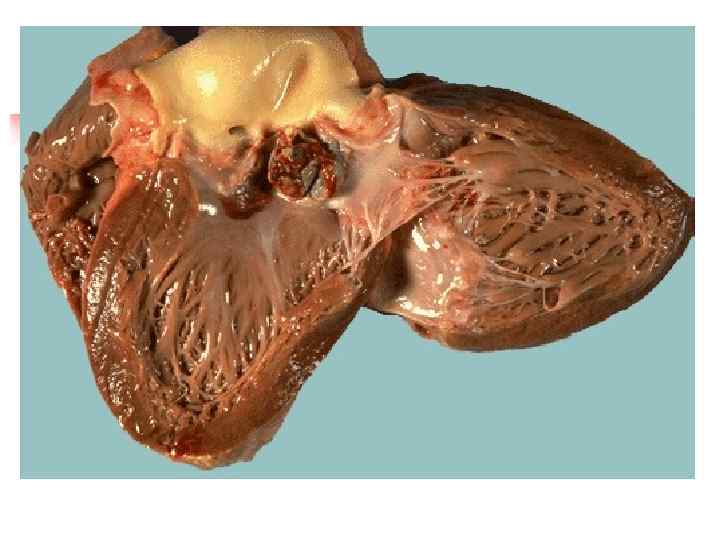

n n Септический или бактериальный эндокардит (sepsis lenta) обычно вызывается белым и золотистым стафилококком, зеленящим стрептококком (преимущественно L- формы и мутанты), реже гемолитическим стрептококком, пневмококком, энтерококком, кишечной и синегнойной палочками. Септический эндокардит является результатом гиперергии, по сути септицемией с септическим очагом на клапанах сердца (чаще аортальных). В основе гиперергии лежат реакции гиперчувствительности, обусловленные воздействием циркулирующих в крови токсических иммунных комплексов, которые содержат антиген возбудителя. С циркуляцией в крови иммунных комплексов связаны такие проявления септического эндокардита как генерализованные васкулиты, резкое повышение сосудистой проницаемости, тромбоэмболический синдром, клеточные реакции стромы и др.

n n Бактериальный эндокардит разделяют по характеру течения (острый около 2 недель, подострый - до 3 мес. , затяжной - многие месяцы и годы) и наличию или отсутствию фонового заболевания (развивающийся на порочных клапанах - вторичный, составляет до 80% случаев; и первичный - на интактных клапанах). Сердце увеличивается в размерах за счет левого или правого отделов в зависимости от характера порока (аортального или митрального), пораженные клапаны склерозированы, резко деформированы и покрыты значительными тромботическими наслоениями.